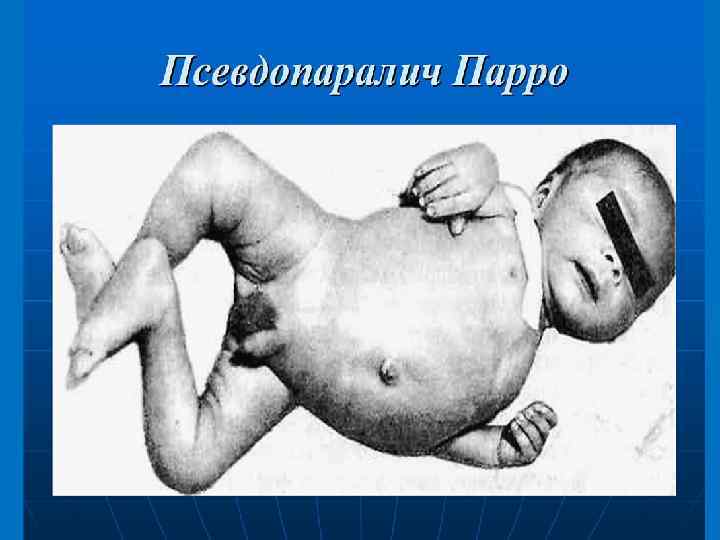

§ § § Периоститы и остеопериоститы Поражаются преимущественно длинные трубчатые кости конечностей, реже – плоские кости черепа. Клинически проявляется в виде нерезко ограниченных болезненных припухлостей. Массивные костные наслоения на передней поверхности большеберцовой кости в результате многократно рецидивирующих и заканчивающихся оссификацией остеопериоститов приводит к образованию серповидного выпячивания и формирования ложных саблевидных голеней. Изменяется форма костей черепа. Наиболее типичны «ягодицеобразный» череп и «олимпийский лоб» .